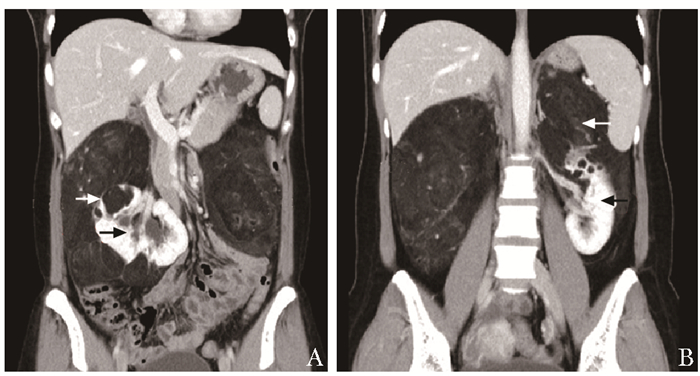

结果   14例AML患者中有1例相对孤立肾合并AML、7例多发AML、8例巨大AML(肿瘤最大直径>7 cm)、6例紧邻肾集合系统或肾门的AML以及2例合并出血破裂史AML, 病情复杂, 手术难度大。采取经腹腔镜或开放肾部分切除或肿瘤剜除术后, 顺利切除肿瘤, 病理检查提示肾AML, 术后定期门诊随访, 行CT扫描均无复发。全部患者术后肾功能保持良好, 术前和术后1个月血肌酐水平分别为(84.1±26.8)μg/ml和(97.5±37.0)μg/ml, 两组数据差异无统计学意义(t=-3.193, P>0.05)。

Results  Among 14 patients with renal AML, 1 had a relative solitary kidney with AML, 7 had multiple AML, 8 had huge AML (the maximum diameter of the tumor >7 cm), 6 had AML adjacent to the renal collection system or the renal portal, and 2 had AML combined with bleeding and rupture history; all cases were complicated and difficult to treat. All operations were successfully performed by laparoscopic or open partial nephrectomy or enucleation of the tumor, and pathological examination indicated renal AML. All patients were regularly followed up and no recurrence was found by CT scanning. The renal function of all patients was well preserved; the concentration of serum creatinine before and 1 month after the operation were (84.1±26.8)μg/ml and (97.5±37.0)μg/ml respectively, without statistically insignificant difference (t=-3.193, P>0.05).